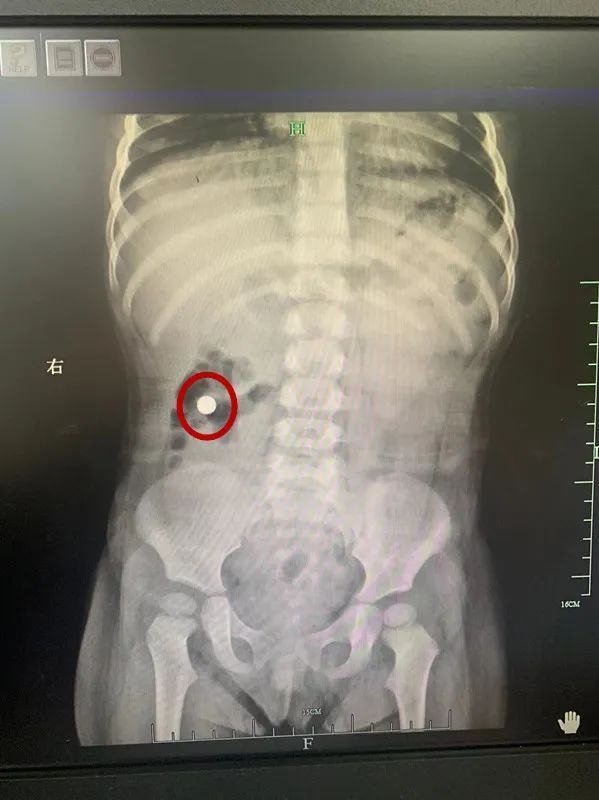

负责接诊的丽水市中心医院儿科医生郑瑞告诉采访人员,事情发生在2月3日上午6时左右。当时,诊室里来了一对神色慌张的父母,带着一个1岁多大的女宝宝。据他们讲述,当天下午,小女儿在家玩耍时,大女儿给了她一支小手电筒,她咬碎了外壳,还把手电筒里的纽扣电池误吞到了肚子里。在庆元当地医院,x光片显示,电池正在孩子的腹部。于是,他们连夜将孩子送到丽水市中心医院就医。

如果孩子不幸吞下电池,症状的严重程度与纽扣电池在体内停留的时间成正比。”像这种情况,一般要立刻安排手术取出电池,以免造成更严重的后果。“郑瑞介绍,鉴于当时患者宝宝没有出现明显的不适症状,状态也比较好,她的父母要求保守治疗。“而且,后续的X光检查结果也显示,纽扣电池一直在往肛门方向移动。”所以,郑瑞给患者口服了蜂蜜和橄榄油,帮助其尽快排出电池。